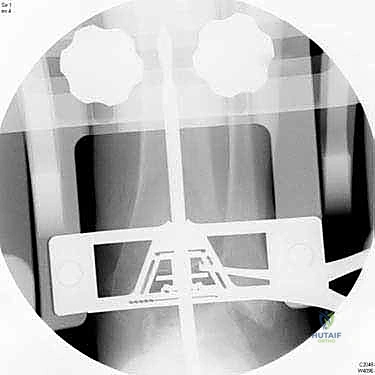

6. التحقق والإغلاق

يتم فحص المدى الحركي للكاحل الجديد وثباته تحت جهاز الأشعة السينية (Fluoroscopy) داخل غرفة العمليات للتأكد من المحاذاة المثالية بنسبة 100%. بعد ذلك، يتم إغلاق الشق الجراحي بغرز تجميلية، ووضع جبيرة ناعمة أو حذاء طبي واقٍ.